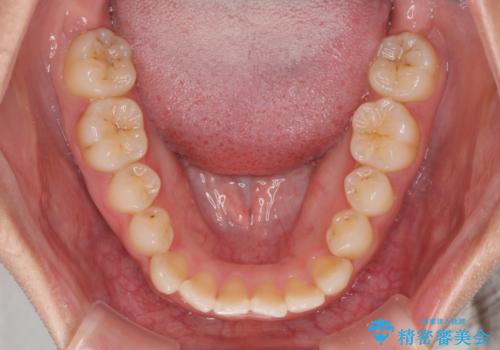

前歯の反対咬合 非抜歯のワイヤー矯正

1年半はかかると思っていた治療期間ですが、反対咬合となっている前歯が思いの外早く動き、僅か9ヶ月で終了させることができました。

前歯を気にせず笑えるようになり、患者様には大変満足していただきました。